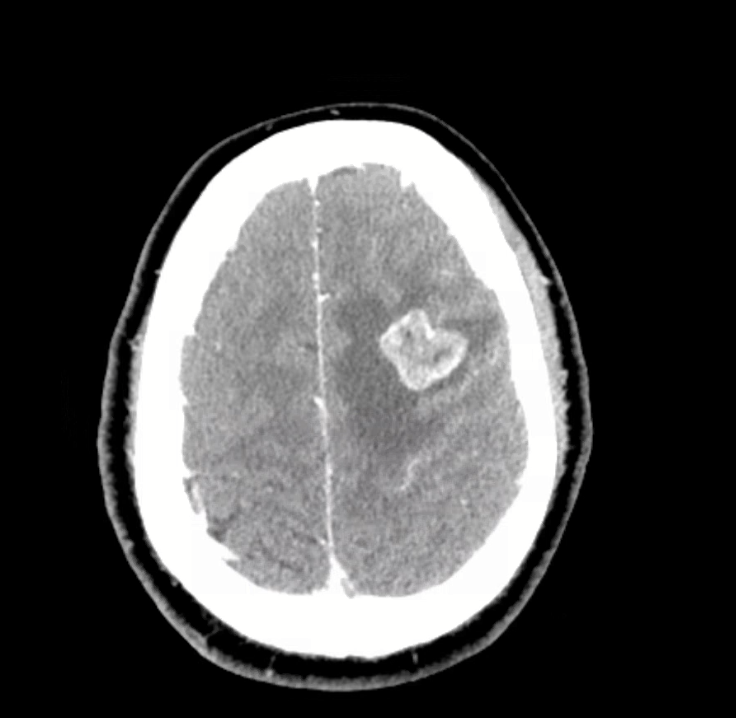

3) Neuro findings—ring-enhancing lesions

- Differential: septic emboli/abscess, nocardia, fungal, TB, parasites, metastases, vasculitis, sarcoid.

- Partner with neuroradiology for pattern nuances; treat seizures but keep searching for the unifying diagnosis.

- Therapy: Targeted TKI (crizotinib) → dramatic radiographic response of miliary lung disease and CNS lesions.

- Teaching point: even “miliary TB-like” lungs + CNS lesions in a 20-something can be driver-positive lung cancer—don’t let age or pattern blind you.